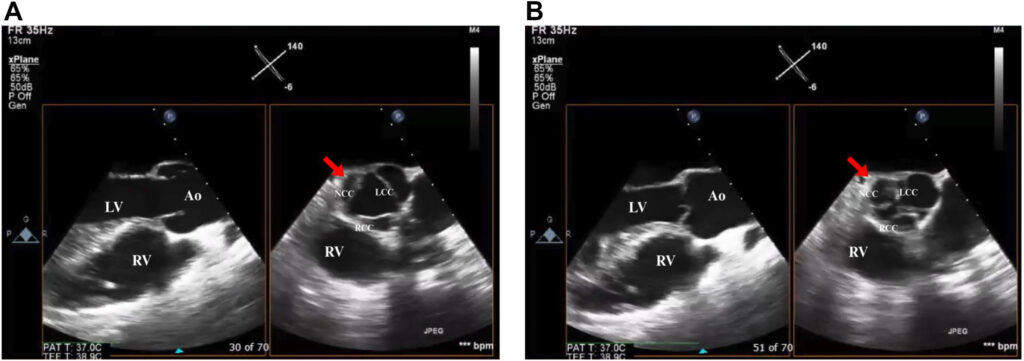

No terceiro dia de admissão, foi realizado ecocardiograma transtorácico cujo resultado demonstrou fração de ejeção (FE) de 60% e uma valva aórtica trivalvular com perfuração do folheto não coronariano e insuficiência aórtica (IAo).

Indicada abordagem cirúrgica e ecocardiograma transesofágico antes do procedimento mostrou prolapso do folheto coronariano direito, perfuração do folheto coronariano esquerdo e também no não coronariano, além de fluxo reverso holodiastólico em aorta descendente.